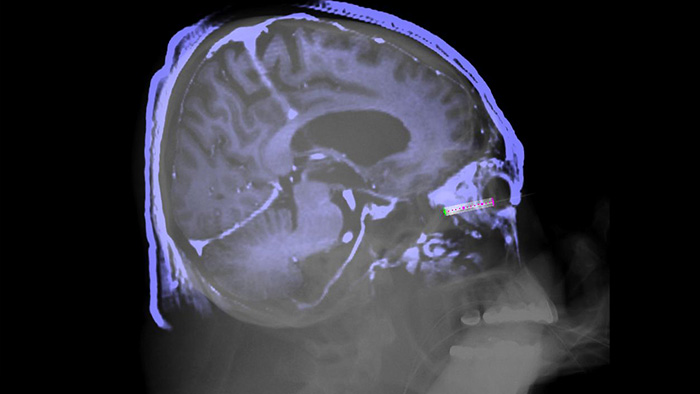

Die SmartCT Lösung ergänzt unsere umfassenden interventionellen 3D-Tools um aktive Benutzerunterstützung, welche der unkomplizierten Erfassung von 3D-Bildern im interventionellen Labor dient, sodass diese allen klinischen Anwendern ganz unabhängig von ihrem Erfahrungsniveau zugänglich sind.1. Nach der Erfassung werden die 3D-Bilder in Sekundenschnelle automatisch auf dem Touchscreen-Modul in der entsprechenden Rendering-Betriebsart angezeigt. Hier haben Anwender dann auch Zugang zu Tools für erweiterte 3D-Darstellungen und -Messungen.

SmartCT Soft Tissue bietet eine Cone-Beam-CT-Erfassungstechnik (CBCT), die durch Schritt-für-Schritt-Anleitungen, erweiterte 3D-Darstellungs- und Messwerkzeuge, die alle auf dem Touchscreen-Modul am Tisch zugänglich sind, ergänzt wird. Damit Ihre CBCT-Bilder auf Anhieb gelingen und Ihr Arbeitsablauf effizient gelingt, werden Sie durch die wichtigsten Schritte geführt.